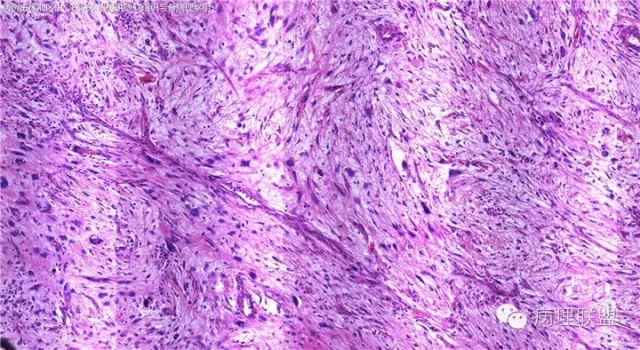

梭形细胞恶性肿瘤。低倍示瘤细胞排列呈束状,席纹状。部分区富裕黏液,黏液区细胞稀疏,内见较多线状,弓形,及分支状薄壁血管。中高倍示瘤细胞多形性,异型性明显,核分裂易见。部分细胞胞浆丰富红染。背景中可见炎细胞浸润!根据形态学及发病部位可能诊断有

1:MPNST

2:GIST

3:高级别脂肪肉瘤或去分化脂肪肉瘤

4:肌源性肉瘤

5:高级别纤维肉瘤

6:高级别肌纤维母细胞肉瘤

7:恶性SFT

8:未分化肉瘤。

根据目前组化结果考虑倾向去分化脂肉或未分化肉瘤。需两者估计只有通过多取材仔细寻找有无高分化脂肉的区域!若确实无个人觉得诊断未分化肉瘤即可!任何一种肉瘤的终末阶段都是未分化肉瘤!高度恶性临床治疗及预后没有太大差别!